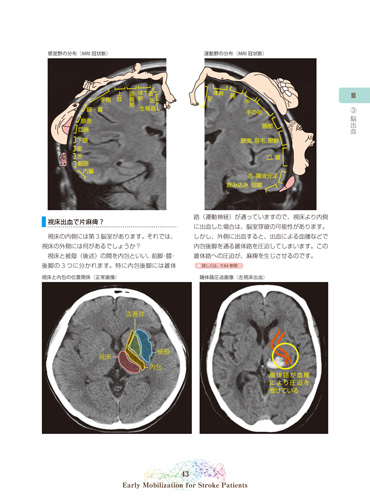

3. 脳出血